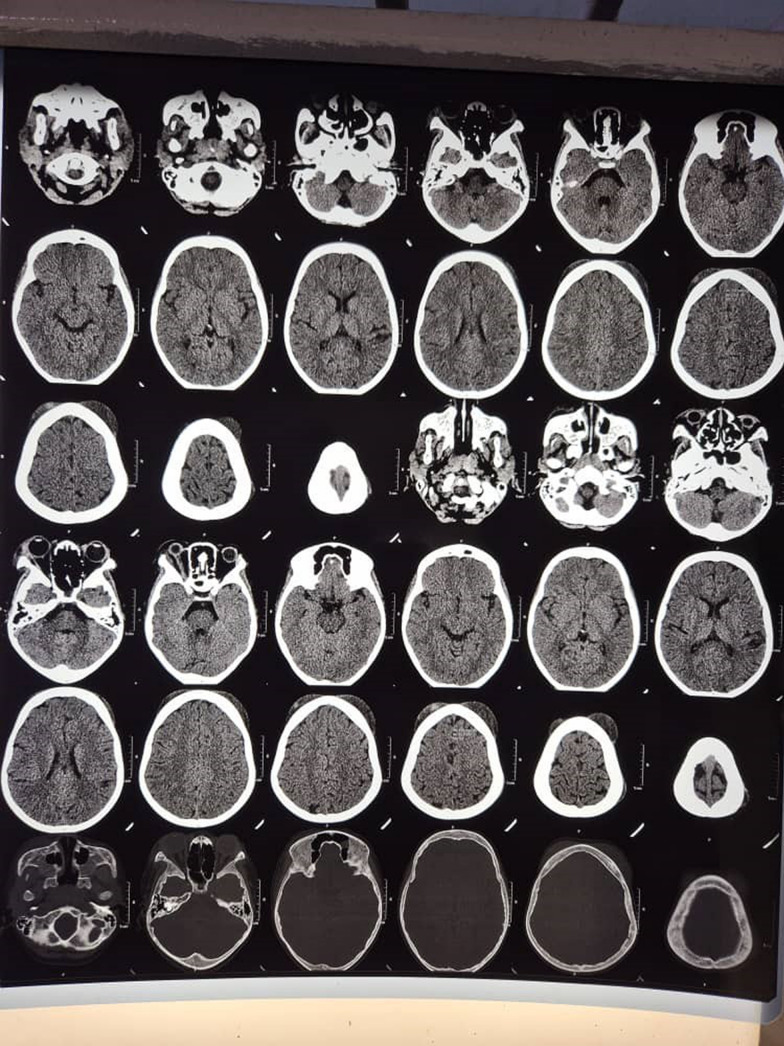

Case presentation: A 9-year-old Ugandan male patient known to have sickle cell anemia presented to our pediatric emergency unit with areas of swelling of the head that progressed in a couple of hours to involve the right eye and were associated with a low-grade fever but no headache. A diagnosis of acute soft head syndrome complicated by orbital compression syndrome was made. The patient was treated conservatively with fluids, analgesia, steroids and prophylactic antibiotics. The orbital compression syndrome was complicated by a corneal ulcer; however, vision was retained in all visual fields due to the corneal ulcer's location below the pupillary axis.